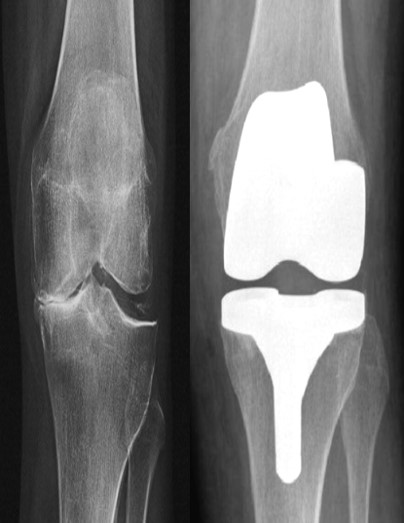

Приклад 1. Хвора Б. 52 років. Діагноз: Ревматоидній Деформівний IVст. гонартроз, вальгусна деформація колінногосуглоба.  Нестабільність та руйнування компонентів ендопротеза. Хворій виконано ревізійне ендопротезування: видалення компонентів ендопротезу, виявлений дефект латерального  виростку великогомілкової кістки тип Т3А за класифікацією АОRI [G.A. Engh, C.H. Rorabeck, 1997]. Під час операції виконана кісткова пластика дефекту латерального виростка лівої великогомілкової кістки. Використаний ендопротез колінного суглоба з подовжувачами .